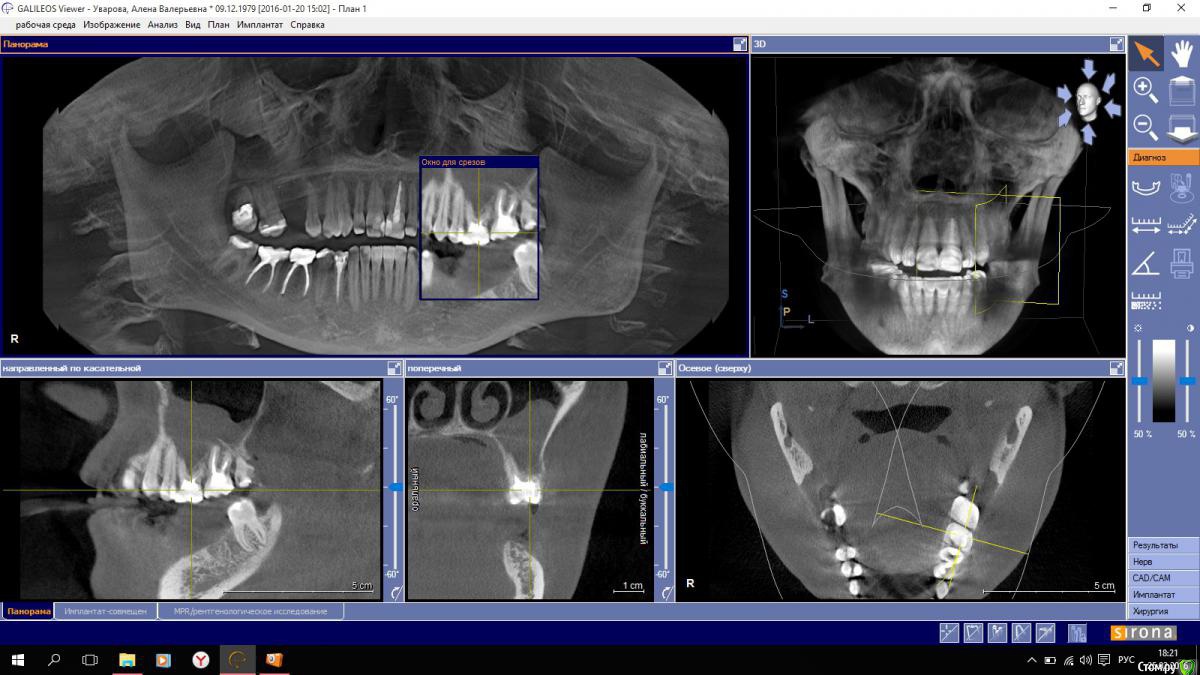

снимок показал воспаление в гайморовой пазухе слева, на ваш профессиональный взгляд 27 зуб следует удалить , как источник инфекции?

или можно его вылечить?

post-46817-0-49829900-1456415880_thumb.jpgpost-46817-0-08447500-1456415884_thumb.jpg